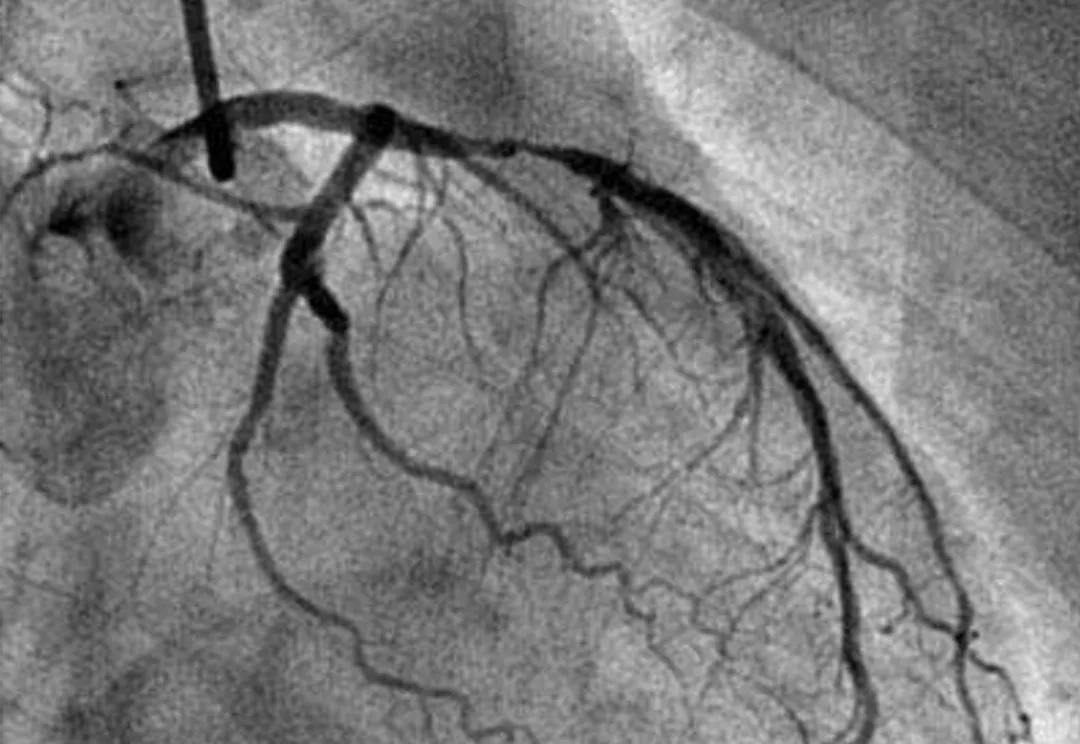

另外,很多检查使用的都是一次性耗材,而且这些耗材的价格本身就贵。 就拿冠状动脉造影来说吧,这个检查的费用在5000元左右。之所以贵,一方面是因为它需要用到很多的一次性耗材,另一方面这些一次性耗材的价格比一般的一次性耗材高得多。